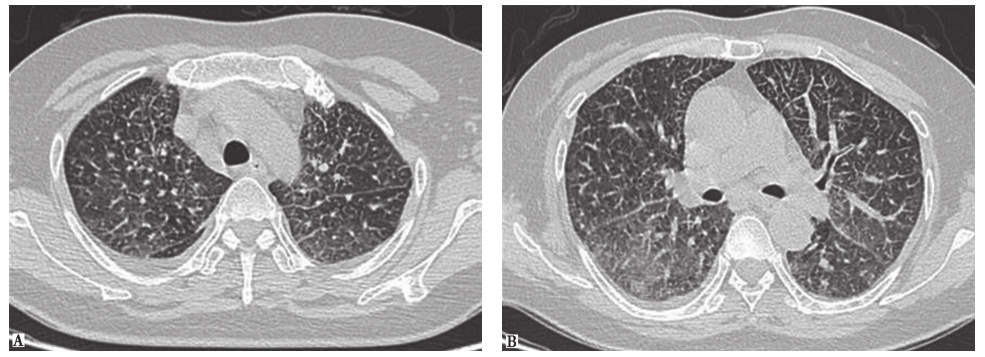

患者经泼尼松(20mg,每天2次)口服治疗,并且脱离原有工作环境,1个月后复查胸部HRCT示两肺磨玻璃影及小结节影较前进一步吸收(图17),咳嗽、气喘症状明显缓解。

图17泼尼松治疗1个月后胸部HRCT表现

HRCT显示磨玻璃影及小结节影进一步减少,双肺胸膜下少量小结节影